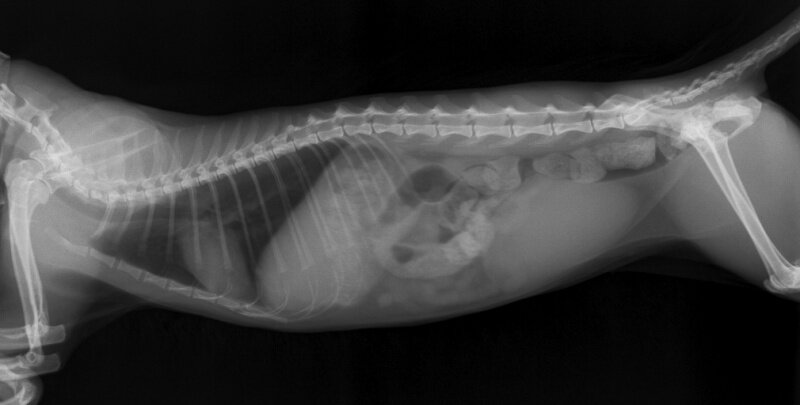

Мы взяли кошку на стационар. Сделали глубокую клизму, дали вазелинового масла и оставили в тишине. Но ни через 15 минут, ни через час, ни через 5 кошка не сходила в туалет. Переделали УЗИ и рентген. Все стояло колом и не хотело двигаться. Зато в процессе увидели, что петли кишечника лежат не так, как положено. Решили провести диагностическую лапароскопию. Это тогда, когда рассекают брюшную полость и прощупывают каждый миллиметр кишечника на предмет различных патологий.

Рентегновский снимок